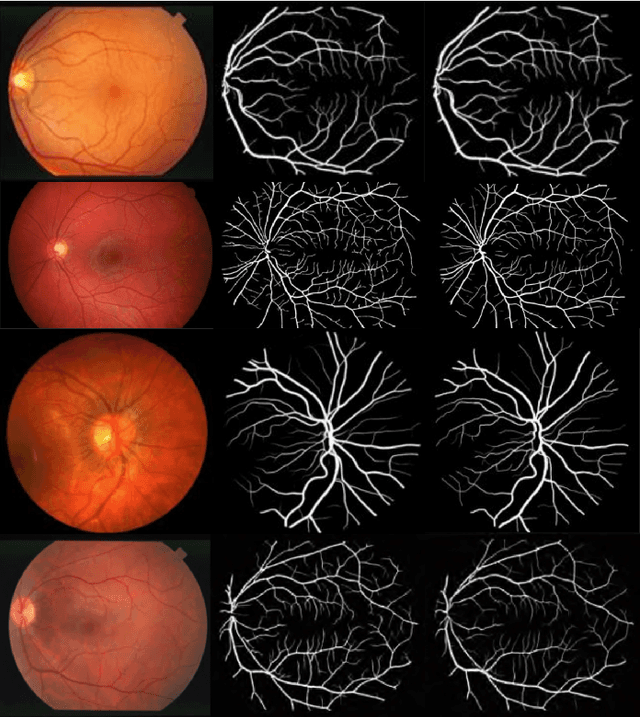

Segmentation plays a crucial role in diagnosis. Studying the retinal vasculatures from fundus images help identify early signs of many crucial illnesses such as diabetic retinopathy. Due to the varying shape, size, and patterns of retinal vessels, along with artefacts and noises in fundus images, no one-stage method can accurately segment retinal vessels. In this work, we propose a multi-scale, multi-level attention embedded CNN architecture ((M)SLAe-Net) to address the issue of multi-stage processing for robust and precise segmentation of retinal vessels. We do this by extracting features at multiple scales and multiple levels of the network, enabling our model to holistically extracts the local and global features. Multi-scale features are extracted using our novel dynamic dilated pyramid pooling (D-DPP) module. We also aggregate the features from all the network levels. These effectively resolved the issues of varying shapes and artefacts and hence the need for multiple stages. To assist in better pixel-level classification, we use the Squeeze and Attention(SA) module, a smartly adapted version of the Squeeze and Excitation(SE) module for segmentation tasks in our network to facilitate pixel-group attention. Our unique network design and novel D-DPP module with efficient task-specific loss function for thin vessels enabled our model for better cross data performance. Exhaustive experimental results on DRIVE, STARE, HRF, and CHASE-DB1 show the superiority of our method.